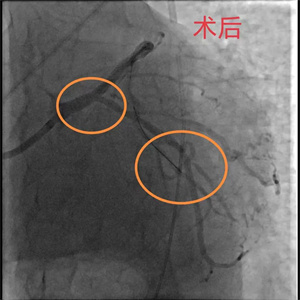

关键时刻,心血管内科副主任医师吴义权、主治医师孙春根、夏秋旺和介入团队紧密协作,在IABP的保护下快速开通血管。术后,患者转入心血管内科监护病房。在医护团队的精心医治和悉心照料下,现已平安出院。

池州市第二人民医院心血管内科在近些年实现了迅猛发展,冠脉介入技术水平持续提升。目前,已常规开展分叉病变、左主干病变、钙化病变、慢性闭塞等复杂冠状动脉介入技术。展望未来,我们将一如既往地致力于提升技术服务能力,为更多胸痛患者祛除病痛,送去健康福祉。